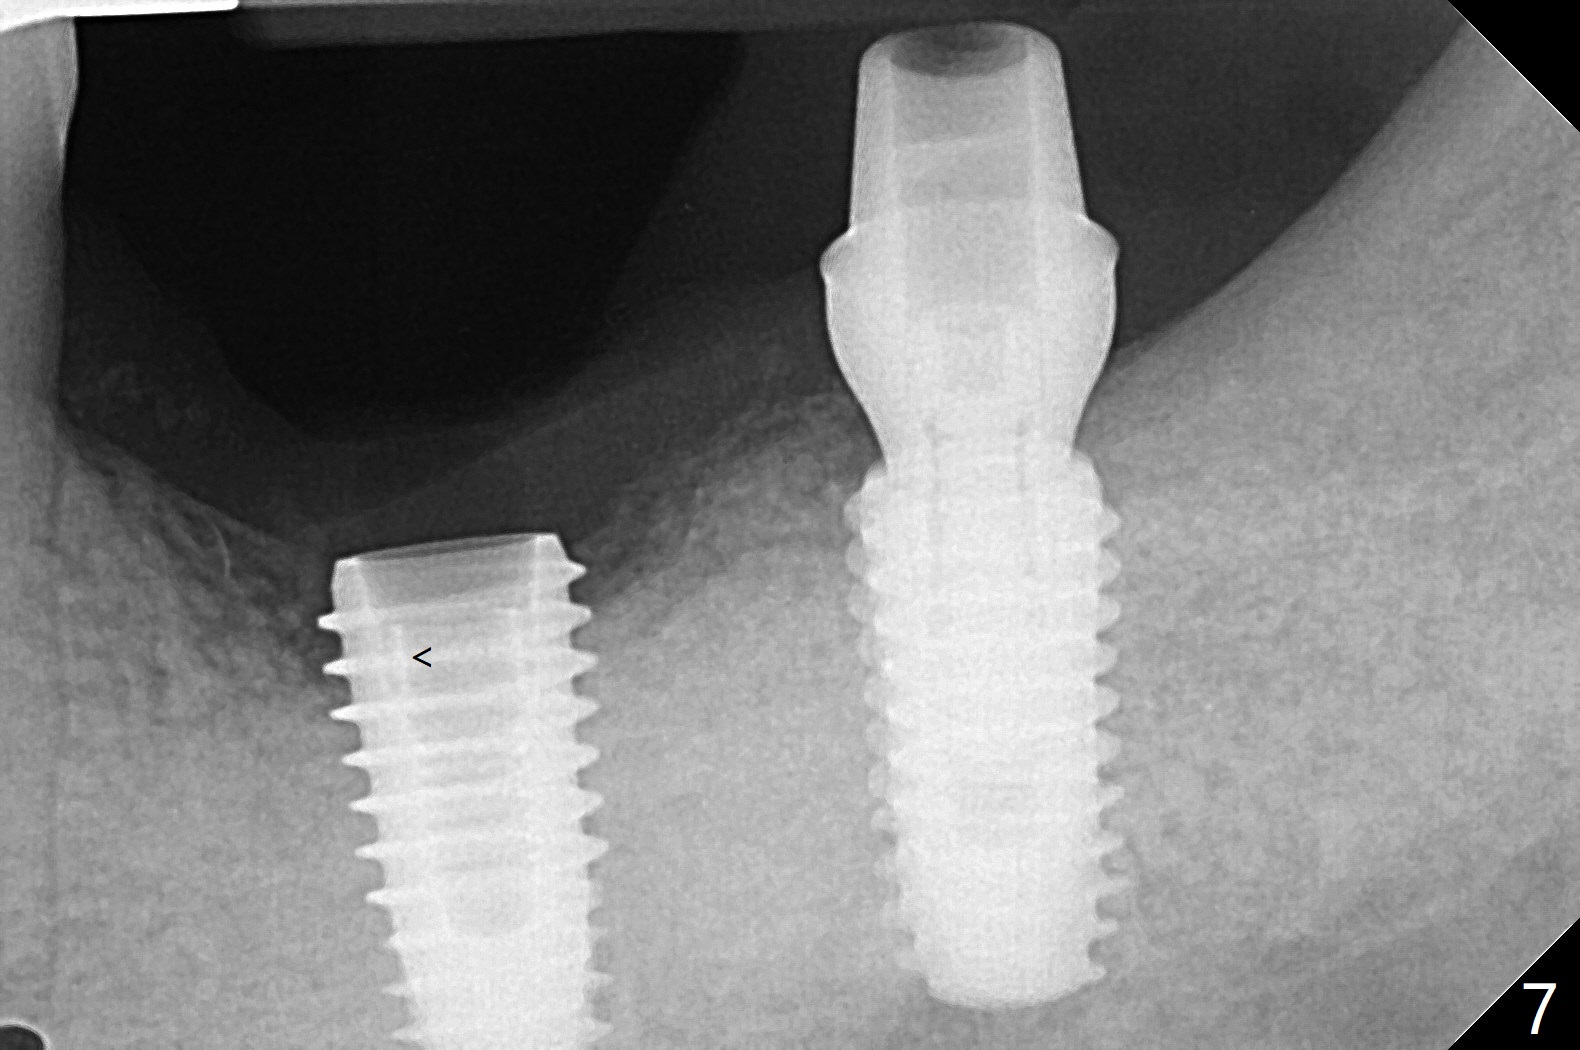

After finishing osteotomy with guide, a 5x14 mm tissue-level implant tap is used without guide because of limited mouth opening. It is not parallel to the implant at #19 (Fig.1). A bone-level implant is barely able to be placed with guide; it is parallel to #19 implant (Fig.2). Pre- and intra-op exam confirms periimplantitis at #19. In addition the horizontally impacted #17 has caries. A large incision is made for #19 debridement and bone graft. #18 bone graft (Fig.2 *) and #17 extraction and Osteogen plug (O) placement. Postop CT shows poor trajectory of #19 implant (Fig.3 (coronal section) free hand placement), which is associated with screw loosening and periimplantitis (lingual (L) threads supracrestal). In contrast #18 implant has good trajectory and placement level (Fig.4). The mesial defect of #19 seems to have been repaired and the implant at #18 osteointegrates 7.5 months postop (Fig.5). The wound at #19 heals except a small slit 7.5 months postop (bone graft, Fig.6). When the incompletely seated healing screw (Fig.2,3) is removed during uncover, it is difficult to place a cemented abutment. A healing abutment is placed instead. In fact the hex of the abutment fractures within the implant well (Fig.7,8 < (due to burial of 1.2 driver inside the abutment and bruxism)). Because of the deeply placed implant, incision is made and surgical long fissure bur is used to section the lingual (Fig.9 L) portion of the hex. When the buccal (B) portion of the hex is being sectioned, the hex dislodges by itself. There is no problem to insert a cemented abutment (Fig.10). Later a longer cuffed abutment is placed and bone graft is placed around the coronal threads (Fig.11 *). The bone graft around #19 implant looks stable 2 weeks post 2nd grafting (Fig.12). Return to Prevent Molar Periimplantitis (Protocols, Table) No Deviation Screw Xin Wei, DDS, PhD, MS 1st edition 02/10/2020, last revision 02/26/2021